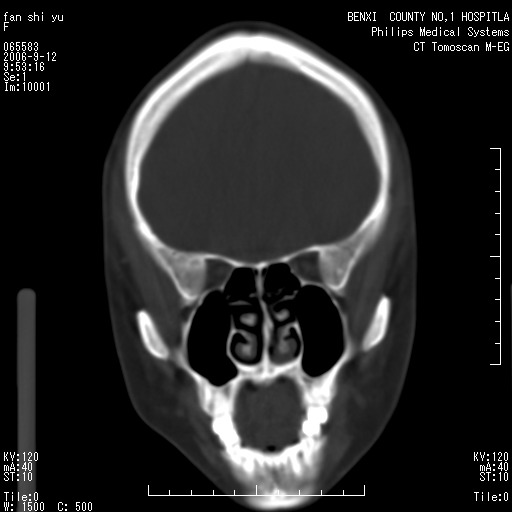

标题: CT4607:看看这个头颅冠状位。

女,22岁,自觉头顶部质硬包块.

巨大蛛网膜粒压迹。

巨大蛛网膜粒压迹